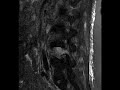

Pathologic Fracture

There is a compression deformity of the L4 vertebral body with near complete replacement of the normal bone marrow signal that also extended into the posterior elements. Additionally, there is expansion of the epidural space with solid enhancing tissue along and partly contiguous with the L4 vertebral body cortex. This finding was consistent with a pathologic fracture in a patient with known metastatic breast cancer and numerous additional spine lesions.